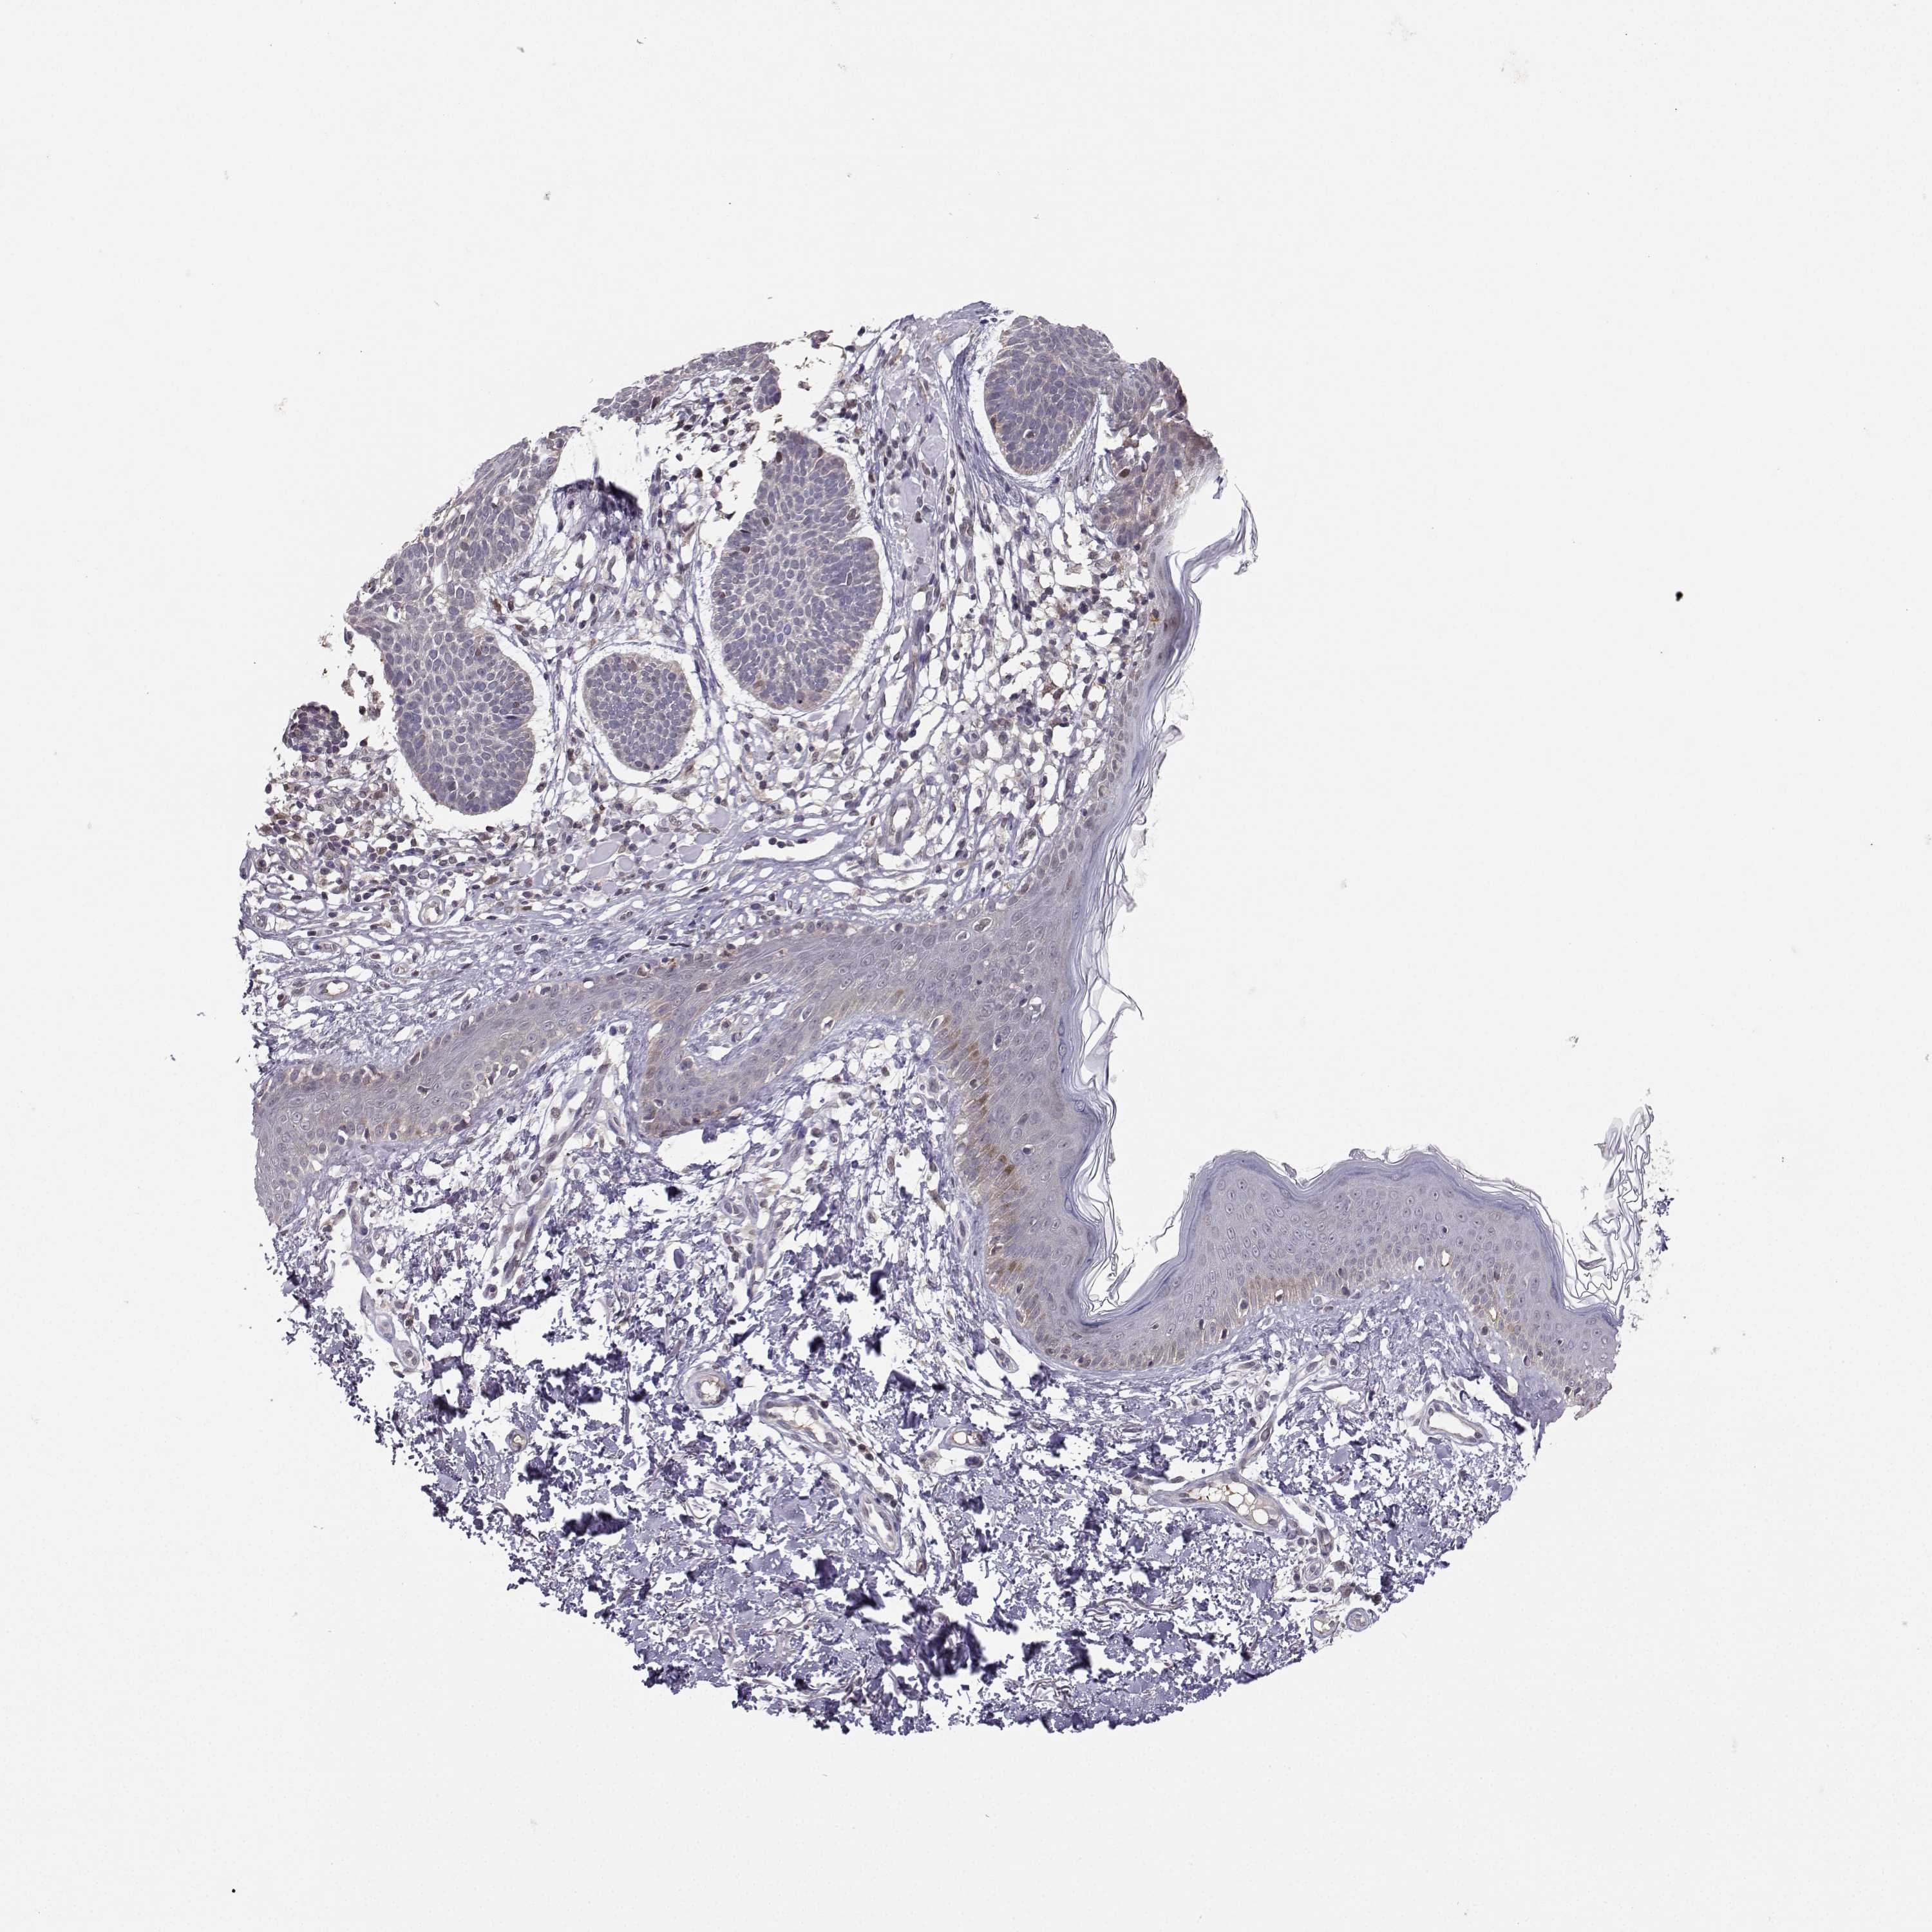

SKIN CANCER - Protein expressioni

A mouse-over function shows sample information and annotation data. Click on an image to view it in a full screen mode. Samples can be filtered based on level of antibody staining by selecting one or several of the following categories: high, medium, low and not detected. The assay and annotation is described here.

Antibody stainingi

Antibody staining in the annotated cell types in the current human tissue is reported as not detected, low, medium, or high, based on conventional immunohistochemistry profiling in selected tissues. This score is based on the combination of the staining intensity and fraction of stained cells.

Each image is clickable and will lead to virtual microscopy that enables deeper exploration of all samples and also displays staining intensity scores, fraction scores and subcellular localization as well as patient and tissue information for each sample.

Antibody HPA056908

Squamous cell carcinoma, NOS